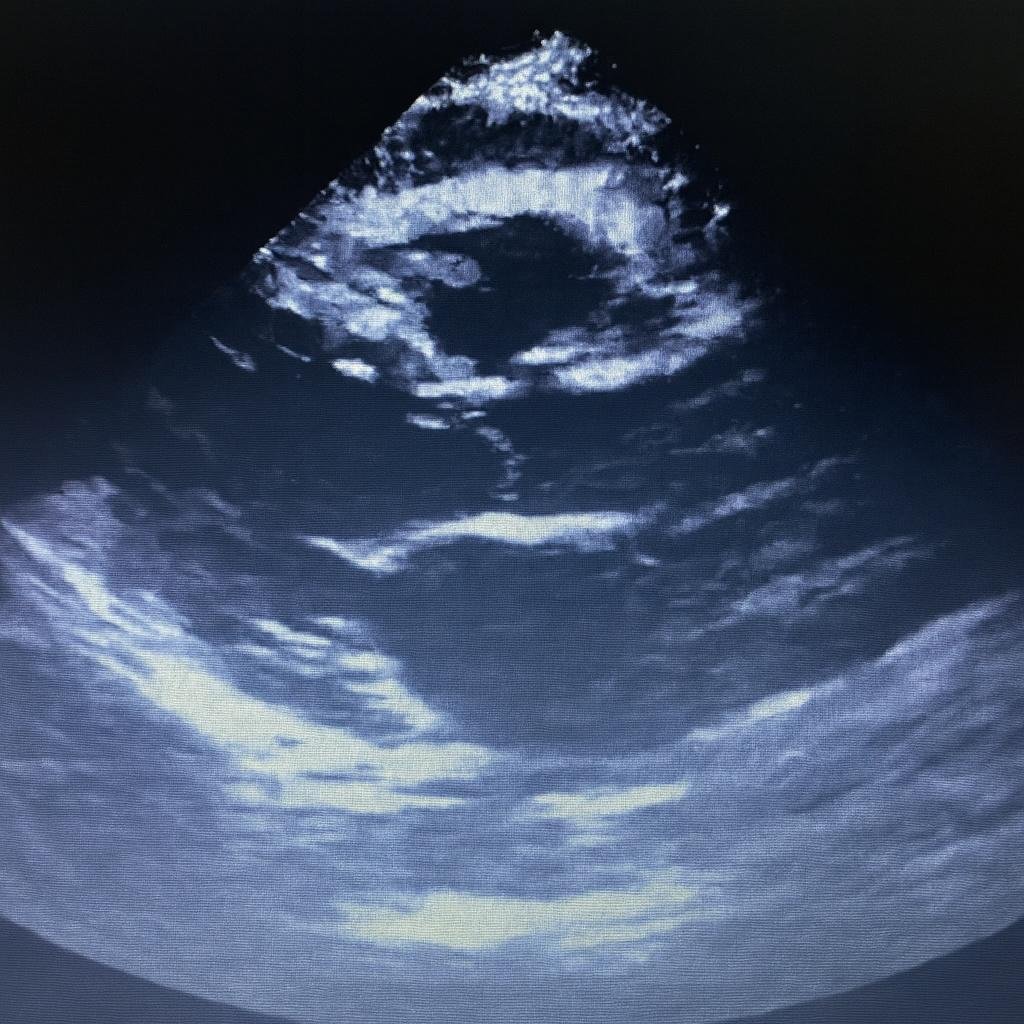

Exame não invasivo que analisa estrutura e funcionamento do coração, identificando alterações de válvulas, músculo cardíaco e fluxo sanguíneo com precisão e segurança.